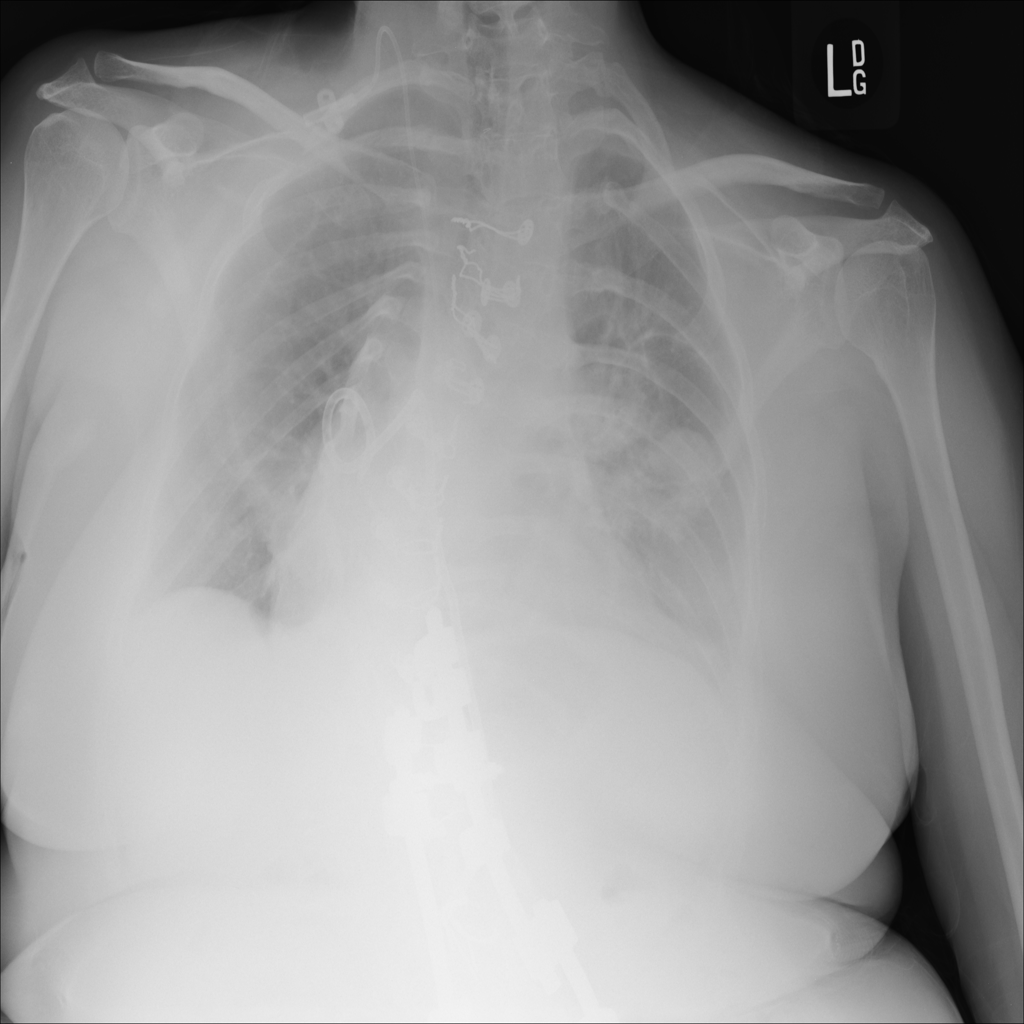

Mass

A mass is a larger focal opacity or lesion seen on the image. It is a descriptive finding that can have several causes and usually needs more imaging or clinical context to characterize.

PAT-D7A5 · IMG-000Mass

PAT-D7A5 · IMG-000

PA